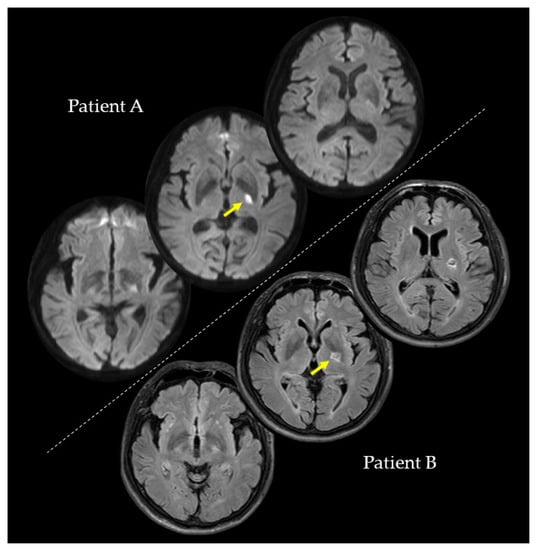

We conducted the investigations of PA and PB at the second, fourth, and eighth weeks after their strokes. In the second week, PA (73 years; female), with a lesion on the left internal capsule due to an ischemic stroke (Figure 1), had a paretic right upper limb with sensorimotor deficits and rarely used her paretic upper limb in her daily life. Regarding the pre-stroke activities of PA, she did housework in general and gardening in her spare time. After the stroke, PA hoped to have improved walking functions. On the other hand, PB (59 years; male), with a lesion on the left putamen due to a hemorrhagic stroke (Figure 1), had a paretic right upper limb with very mild sensorimotor deficits and almost normally used his paretic upper limb in his daily life. Regarding the pre-stroke activities of PB, he did deskwork using a personal computer (PC). After the stroke, PB hoped to have improved hand and finger functions for PC work and writing. PA and PB were right-handed. They had no history or diagnoses of any cognitive impairments, psychiatric disorders, or neurological dysfunctions, except for their post-stroke sensorimotor deficits. PA and PB were assessed for anosognosia through a clinical interview and for neglect using the Catherine Bergego Scale. In the clinical interview for anosognosia, the clinical expert verified whether they were aware of their sensorimotor deficits and whether they could explain these deficits. A summary of the patients’ data is shown in Table 1. This study was conducted with the approval of the Ethics Committee of the Jinjukai Ishikawa Hospital (2018-1). Both participants provided written informed consent.

Figure 1. Magnetic resonance imaging scans showing the lesion sites of Patients A and B. Yellow arrows indicate the lesion sites.